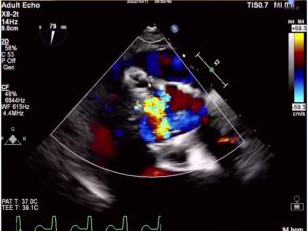

针对本例患者,术者团队介绍了特殊情况,食道超声检查示无冠窦窦壁有囊性结构,考虑存在感染,血流通过无冠窦窦壁喷射到囊腔里面,随后询问病史患者自述有泌尿系感染1月余,故考虑合并感染性心内膜炎,囊性结构是陈旧性赘生物。有专家认为患者有脑梗死病史2月余,系囊性赘生物脱落所致。

与会专家针对食道超声发现的囊性结构展开激烈探讨,对于泌尿系感染和脑梗死的病因认为是赘生物脱落所致,在此情况下,建议该患者不太适合TAVR手术。李飞教授同意现场探讨内容,下一步策略计划再次评估CTA,局部采血后血培养,核磁明确,考虑到患者心衰严重,首先保守治疗后,选择SAVR(外科主动脉瓣置换术)还是抗炎后TAVR具体情况深入分析后在做抉择。但有专家更倾向于外科开胸换瓣,可以进一步分析病理。